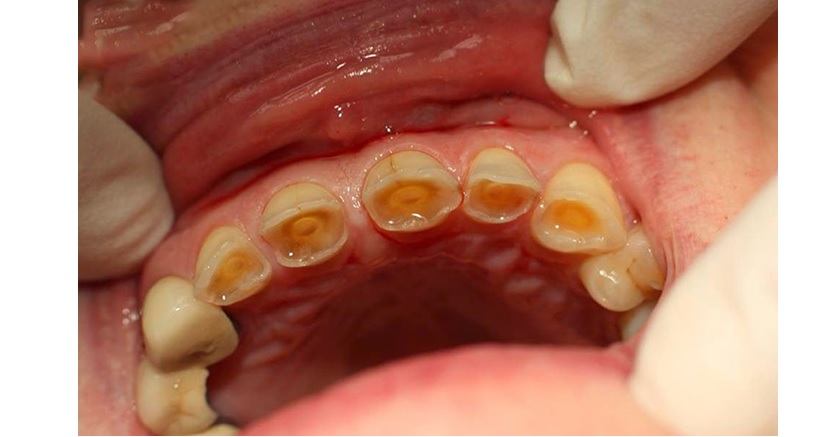

Răng bị mòn mặt nhai là tình trạng bề mặt nhai của răng - đỉnh răng bị mòn do mất mô răng. Tùy vào mức độ men răng bị mòn sẽ tạo ra vết lõm nông hoặc sâu trên bề mặt nhai của răng và mức độ ê buốt khi nhai.

Mức độ mòn mặt nhai của răng được xếp từ nhẹ đến nặng, cụ thể, khi tình trạng mòn chỉ xảy ra ở men răng là mức độ nhẹ và khi tình trạng mòn xảy ra ở ngà răng là mức độ nặng.

- Mất thẩm mỹ: Khi mòn men răng, răng sẽ có màu vàng nâu.